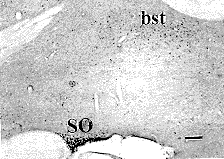

图5 海人藻酸注入Meynert基底核后8h,在视上核中有大量c-fos阳性表达,终纹床核中有少量c-fos阳性表达

Fig. 5 After 8 h of kainic acid injection into the Meynert's basal nucleus, stronger positive expression of c-fos in the supraoptic nucleus and weaker positive expression of c-fos in the bed nucleus of the stria terminals

Fig.1~8 Bright field microphotographs of rat brain, sagital section, bar=50 m m. Aco: Anterior cortical nucleus of amygdala; aod: Anterior olfactory nucleus, dorsal part; Aov: Anterior olfactory nucleus, ventral part; bst: Bed nucleus of stria terminals; CA1: Field CA1 of the Ammon's horn; Ce: central amygdaloid nucleus; CPu: caudate putamen; DG: Dentate gyrus; GP: globus pallidus; ic: Internal capsule; MrD: Marginal division; PCa: anterior part of prepiriform cortex; S: Subiculum; SO: Supraoptic nucleus; TU: Olfactory tubercle.